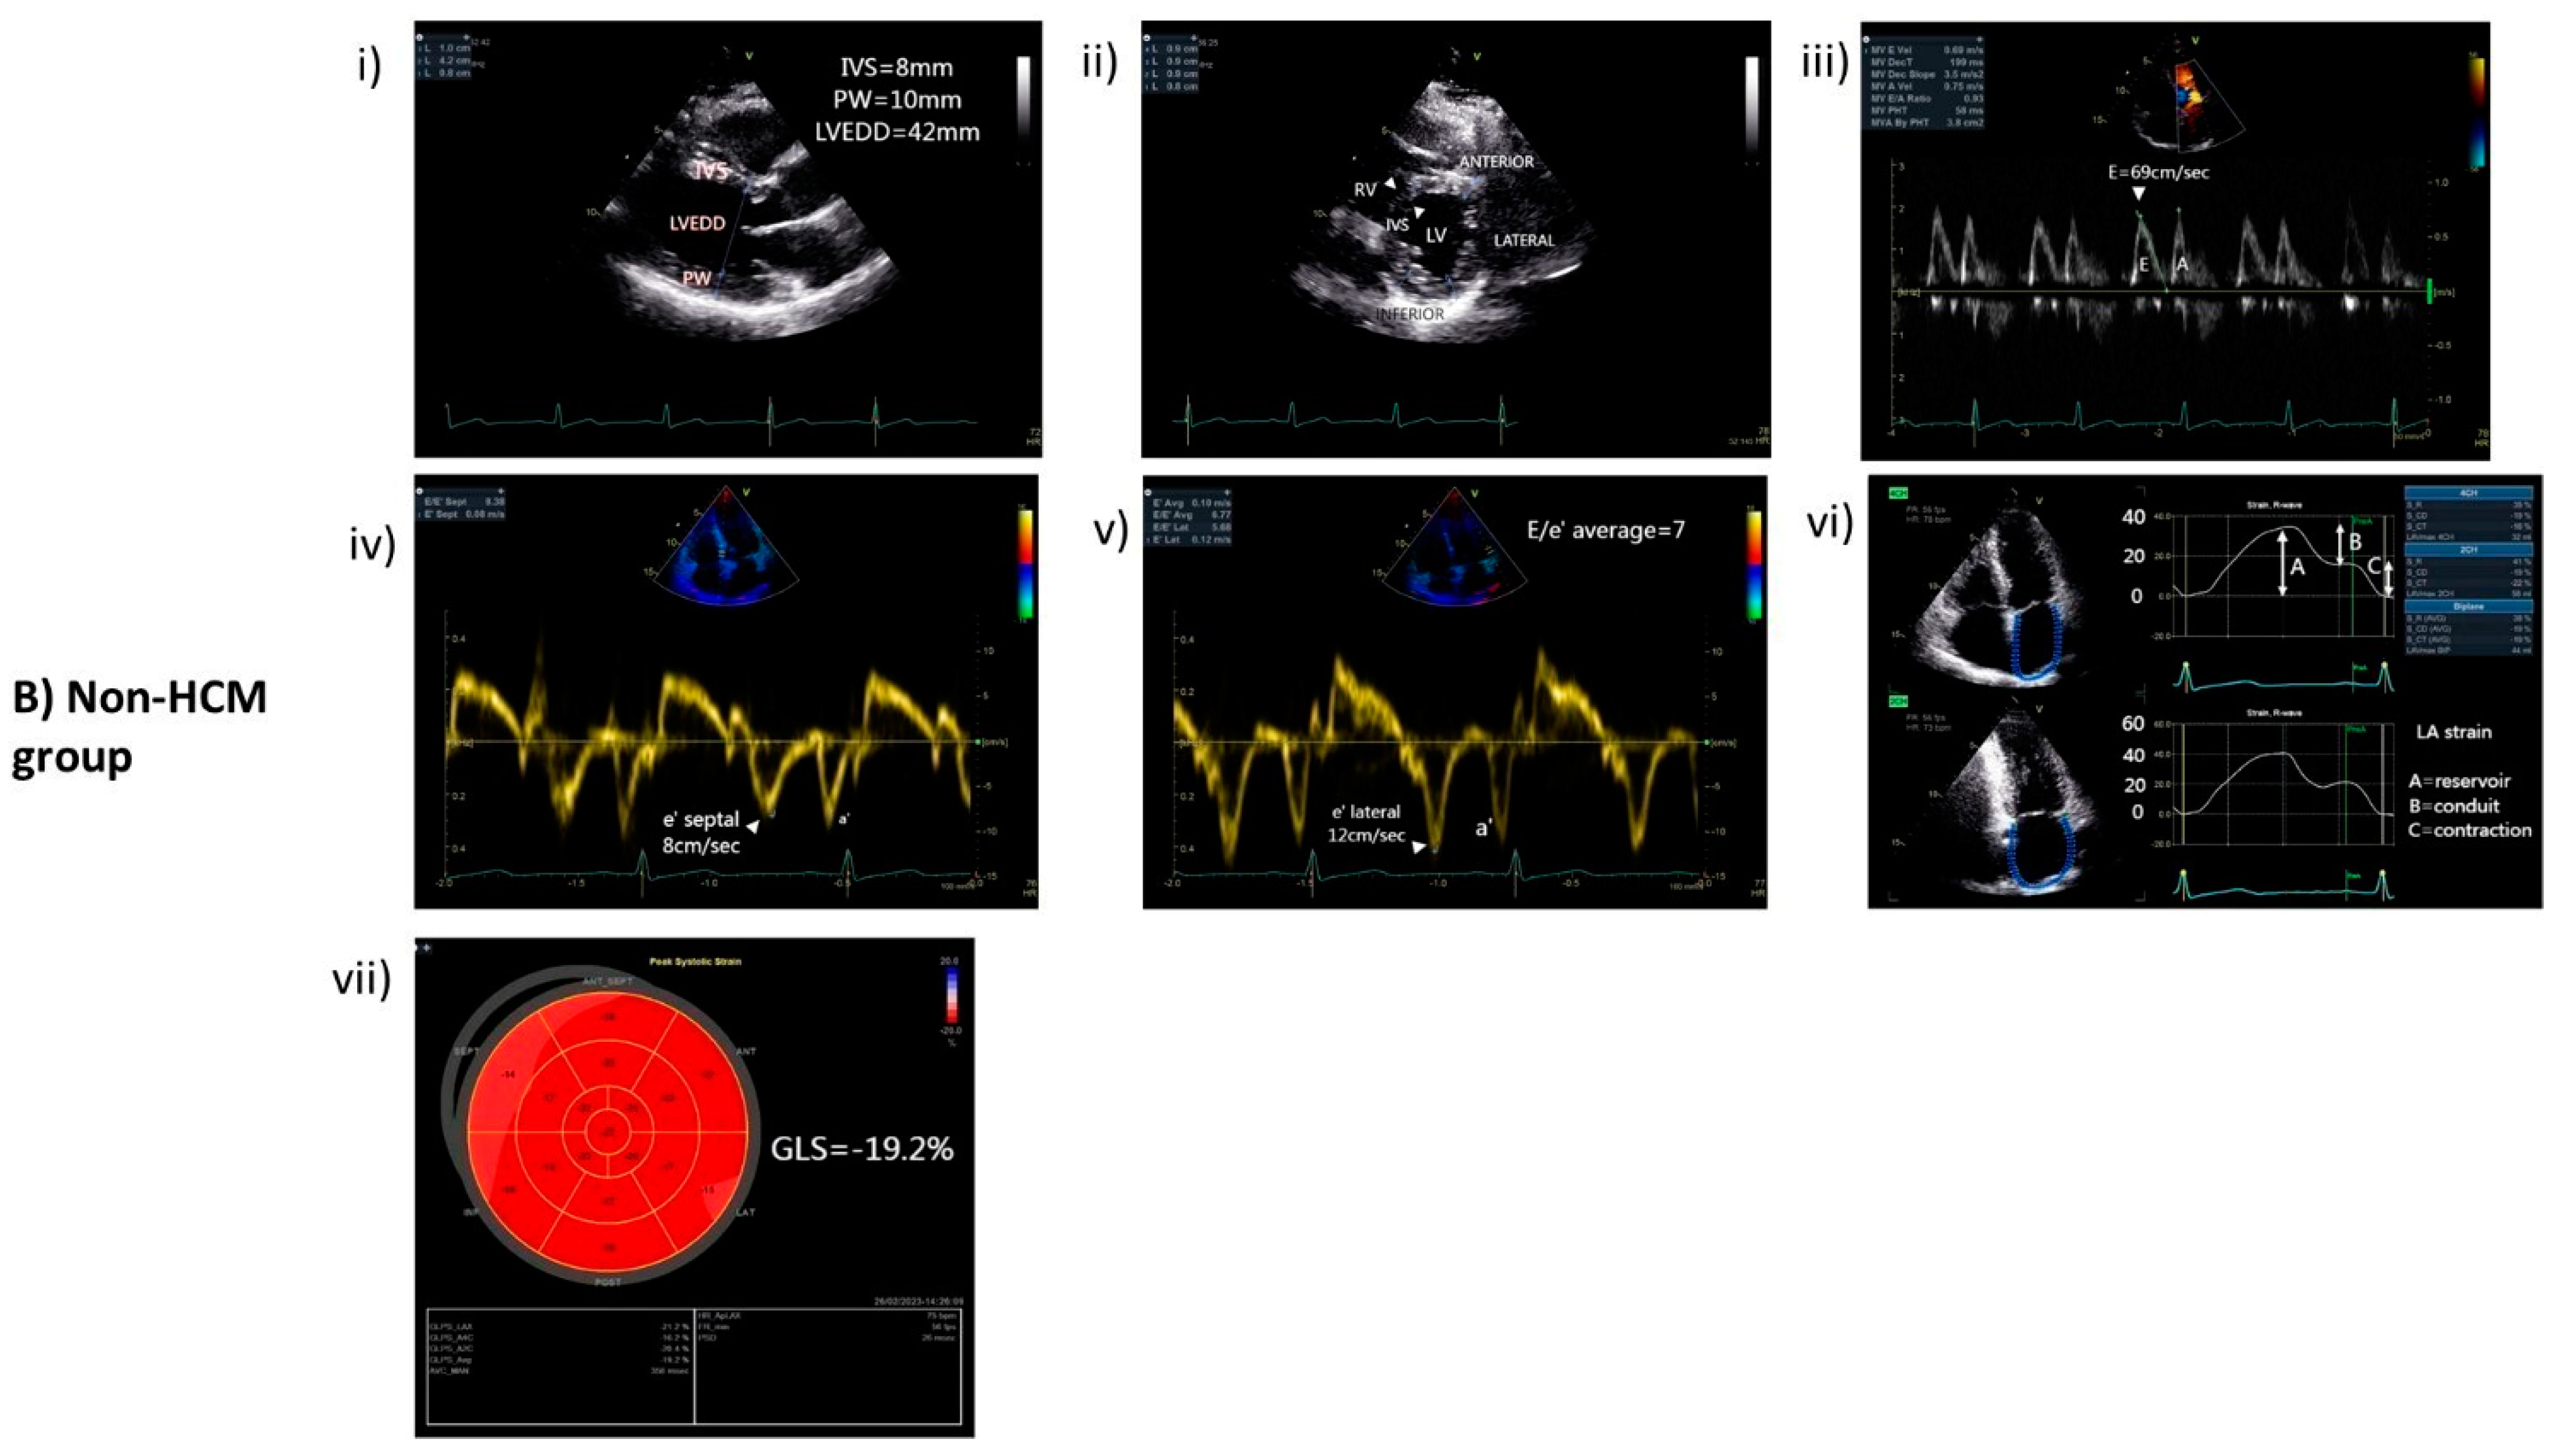

2.2. Echocardiography

3.1. Characteristics of HCM and Non-HCM Group